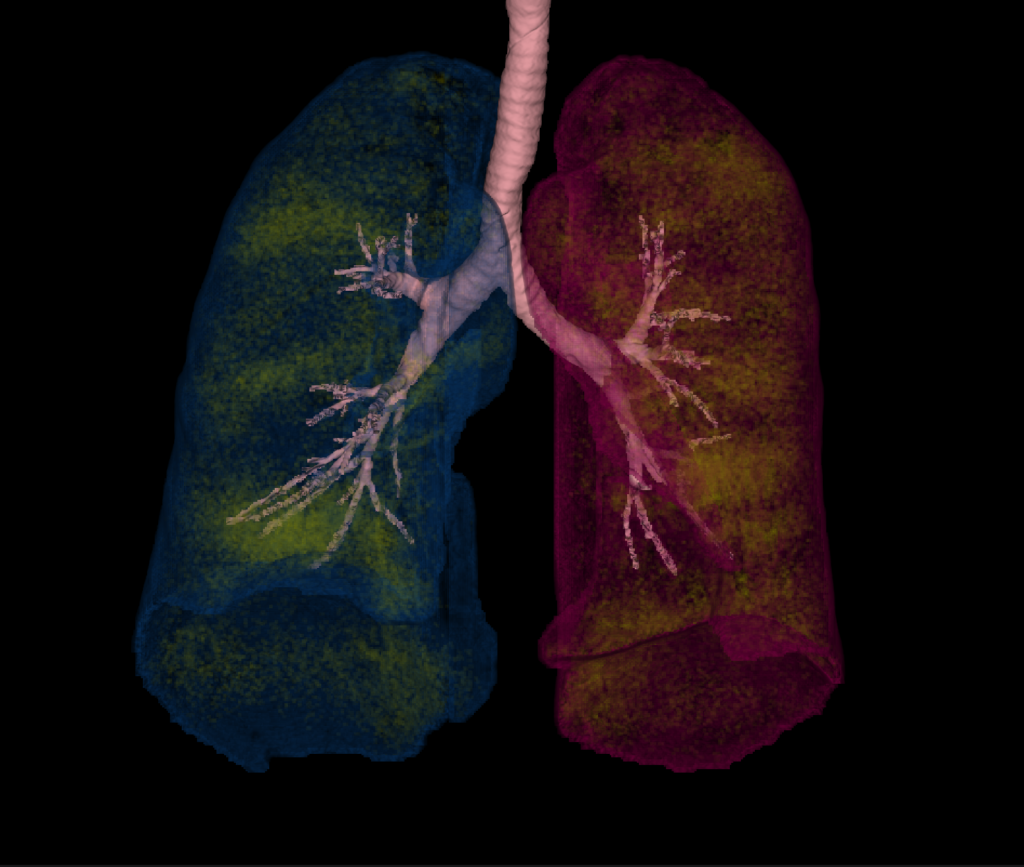

CT Respiratory Analysis

CT Respiratory Analysis provides semi-automatic segmentation of the left lung, right lung, and the bronchial tree.